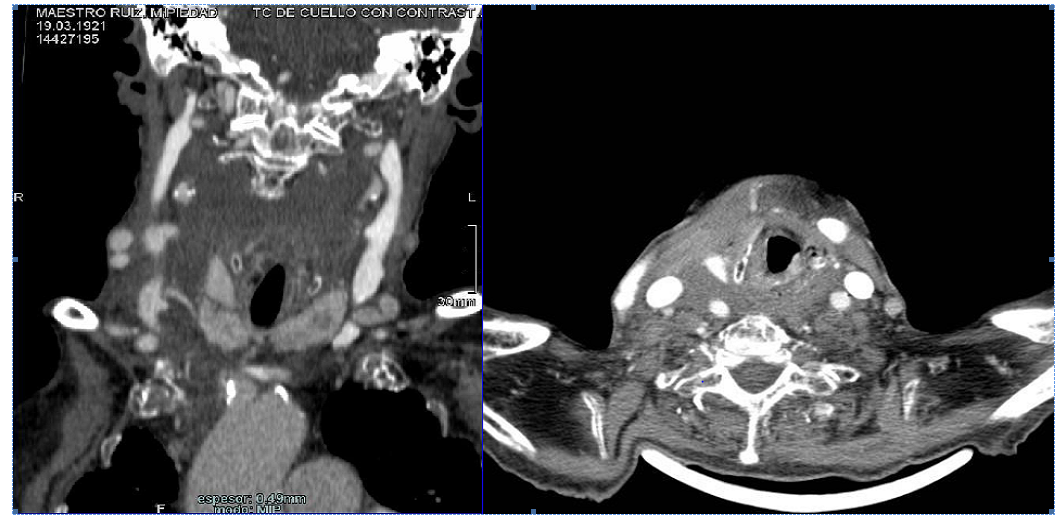

Inmmediately, a cervical CT scan was made that showed a parenchymal laceration of the right thyroid lobe with hematoma evolved in the ipsilateral laterocervical region and in the superior mediastinum without evidence of compatible images with aneurysms in the arterial territories studied (Figure 3).

Figure 3 CT scan that shows cervical hematoma and thyroid disruption.